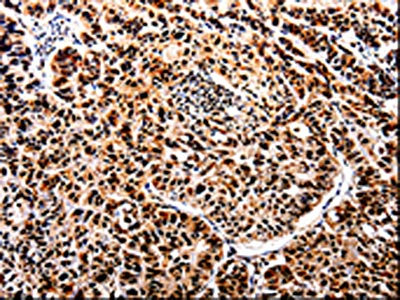

The image on the left is immunohistochemistry of paraffin-embedded Human lung cancer tissue using CSB-PA921015(APIP Antibody) at dilution 1/25, on the right is treated with fusion protein. (Original magnification: ×200)